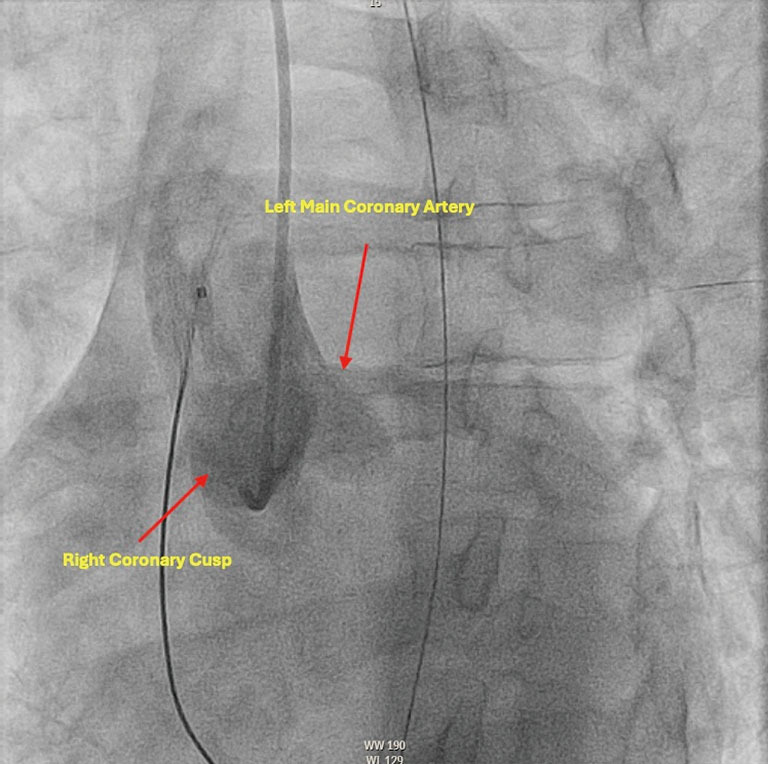

Case description: This report describes a 36-year-old female without prior cardiac history who presented in ventricular fibrillation (VF) electrical storm. While she lacked significant electrolyte abnormalities or ischemia to explain etiology of electrical storm, she incidentally had variant coronary anatomy noted on angiography. After thorough consideration of possible etiologies of storm, selective serotonin reuptake inhibitor (SSRI) intoxication was the most highly suspected etiology. Regarding management of her hemodynamically unstable electrical storm, she was treated with lidocaine, amiodarone, as well as mechanical circulatory support devices including extracorporeal membrane oxygenation (ECMO) and intra-aortic balloon pump (IABP). The patient ultimately was decannulated from ECMO, had IABP removal, and achieved recovery of ejection fraction (EF) to baseline. She was not offered ICD as the etiology of her cardiac arrest was reversable. She was discharged with recommendation to discontinue SSRI and follow up with psychiatry regarding SSRI overdose.